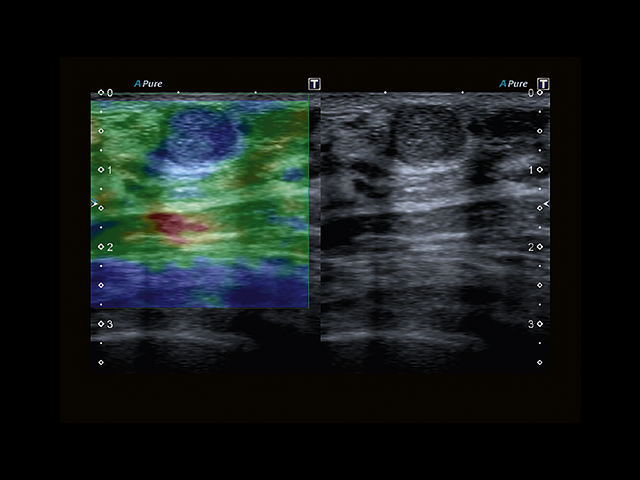

Обновленная версия легендарного УЗ-сканера. Стационарный аппарат экспертного класса Aplio 500 Toshiba NEW, визуализирует анатомические структуры в высоком разрешении. Модель позволяет выявить микрокальцификаты, новообразования, нарушения в работе сердца, сосудов и мышц. Присутствует функция виртуальной эндоскопии, 4D-сканирования, эластометрии тканей, УЗИ с контрастированием. За повышение качества изображения отвечают технологии ApliPure и Superb Microvascular Imaging. Первая задействует возможности пространственного и частотного кодирования, формирует цельный визуальный ряд с сохранением клинических маркеров. Вторая улучшает отображение микрососудистого русла, используя доплеровский эффект. Модель оснащена 21-дюймовым монитором, имеет 4 активных порта. Возможно подключение педиатрических, интраоперационных, лапароскопических и чреспищеводных датчиков.

• MicroPure. Высокотехнологичное решение в области выявления микрокальцификатов – маркеров новообразований злокачественного типа. Маркеры идентифицируются путем изучения затененных изображений целевого участка. Микрокальцификаты отображаются в виде белых пятен.

• D-THI.Режим дифференцированной тканевой гармоники, повышающий качество визуализации глубоко расположенных тканей. Получаемое изображение отличается высокой четкостью, не содержит дефектов в виде «заснеженных» и размытых участков.